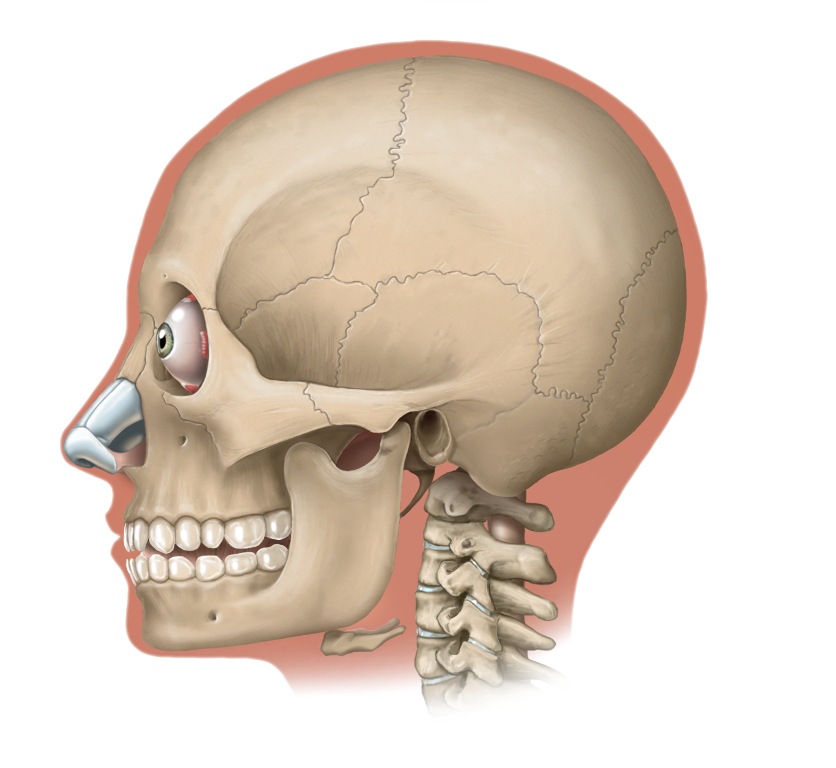

Medical Illustration

All images are works made for hire and are the exclusive property of the client. These are shown as sample purposes of my work only. For licensable work, please see my Illustration Services page.

Contract freelancer for many others, some examples of my work below.

Winner of Award of Excellence for Hockey Anatomy at the 2019 Association of Medical Illustrators Salon